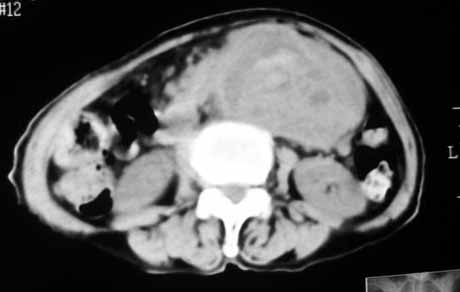

1.中腹部腹主动脉旁可见巨大包块影,其形态似为2个(或分叶),与腹主动脉分界不清,边界较清,其内密度不均匀(稍高、不匀称低密度),腹膜后未见确切肿大淋巴结...性质?考虑腹主动脉瘤可能性大,不排除平滑肌瘤及畸胎瘤可能,建议增强ct;

2.脾门处高密度影块影,原因?

3、脾门区淋巴结钙化。

脂肪肉瘤,平滑肌肉瘤的可能性大。支持!(本例关键是定位,仔细分析,可以观察到主动脉被包埋于肿瘤内,因此可定位于—来源于腹膜后的实性肿瘤。)

腹膜后肿块侵犯腹主动脉及肠系膜上动脉,肿块密度不均,1来源间叶组织肿瘤,2肠系膜恶性肿瘤可能大,

腹膜后占位性病变,腹膜后淋巴结转移,脾门动脉硬化,右肾囊肿。